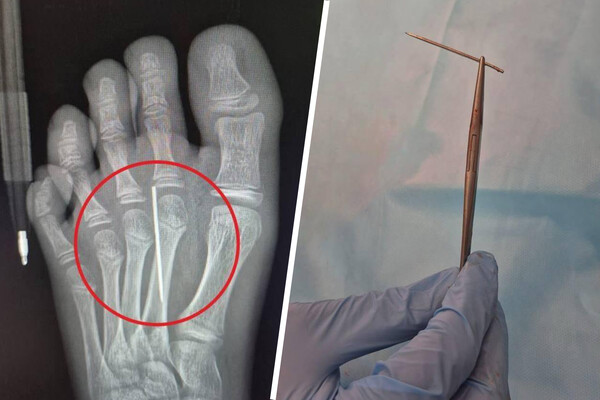

«Врачи визуализировали на рентгене инородное тело и с помощью специального инструмента «Москит» аккуратно извлекли иголку. На все ушло около трех минут», — поделились в Минздраве.